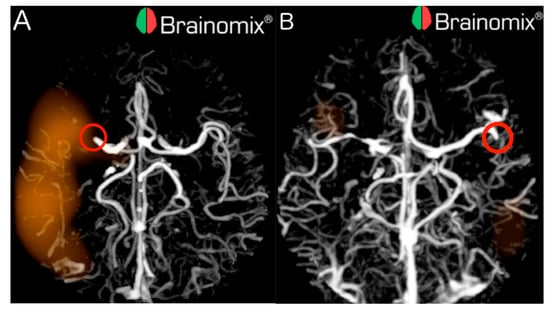

Out of the 70 LVOs, 23 (32.9%) were missed by e-CTA, from which 7 out of 45 (15.6%) were proximal and 16 out of 25 (64.0%) were distal. Examples of proximal and distal LVOs detected by e-CTA are illustrated in Figure 1.

This gave the overall sensitivity for e-CTA of 0.67 (95% CI 0.55–0.78), 0.84 (95% CI 0.71–0.94) for proximal LVOs, and 0.36 (95% CI 0.18–0.57) for distal LVOs. Overall specificity, PPV, NPV and accuracy for e-CTA were 0.95 (95%CI 0.82–0.99), 0.96 (95%CI 0.86–0.99), 0.61 (95%CI 0.47–0.73), and 0.77 (95%CI 0.68–0.84), respectively. The mean processing time was 96 seconds (±23 s).

Figure 1. CTAs of stroke patients with LVOs correctly detected by e-CTA. (A) e-CTA detected proximal LVO of the right MCA-M1 (red circle); (B) e-CTA detected distal LVO of the left MCA-M2 (red circle).